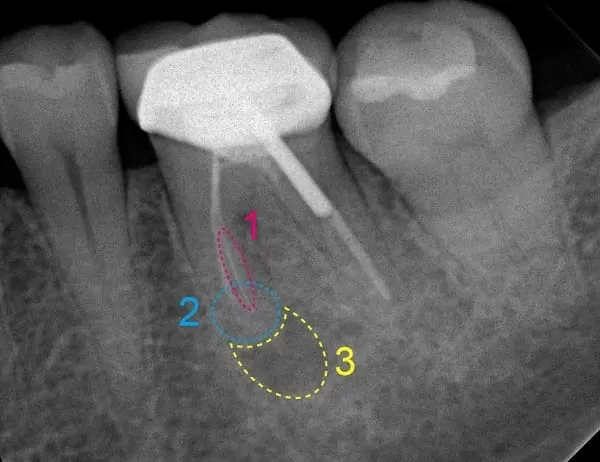

1. 近心舌側的根管(圖中1.),為之前根管治療時,因根管彎曲未能即早判讀,造成根管器械斷裂

2. 因器械斷裂,導致無法有效完整的進行根管治療

3. 近心側的根尖區域(圖中2.),因持續受到慢性發炎刺激也已鈣化,導致無法順利通至根尖

4. 因以上因素,根管皆未能做到理想工作長度和工做寬度,殘留的壞死牙髓未能清潔乾淨,導至根尖開始發炎,甚至細菌蔓延往下侵蝕並感染齒槽骨,因此造成患者的咬痛感以及其他不適(圖中3.)